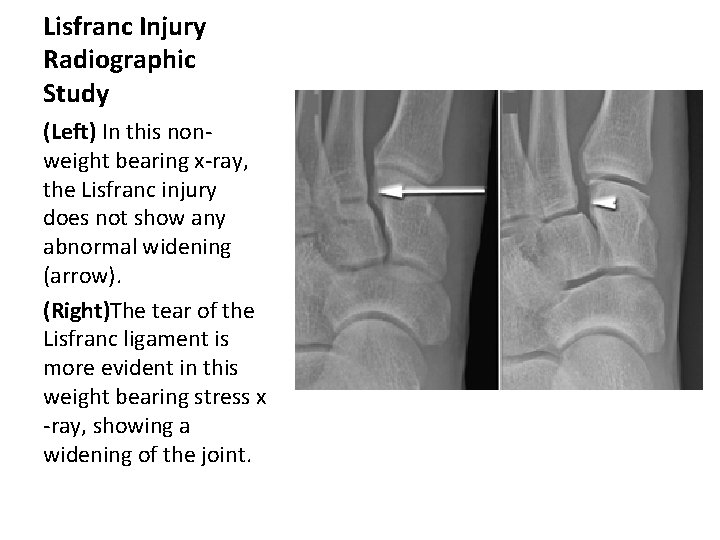

Lisfranc Injury Radiographic Study The initial radiographs of a suspected Lisfranc joint injury should include weightbearing anteroposterior and lateral views, as well as a 30 degree oblique view.

Lisfranc Injury Radiographic Study (Left) In this nonweight bearing x-ray, the Lisfranc injury does not show any abnormal widening (arrow). (Right)The tear of the Lisfranc ligament is more evident in this weight bearing stress x -ray, showing a widening of the joint.

Lisfranc Injury Radiographic Study Flattening of the longitudinal arch, dorsal displacement, or both at the second TMT joint may be observed on lateral weight bearing radiographs